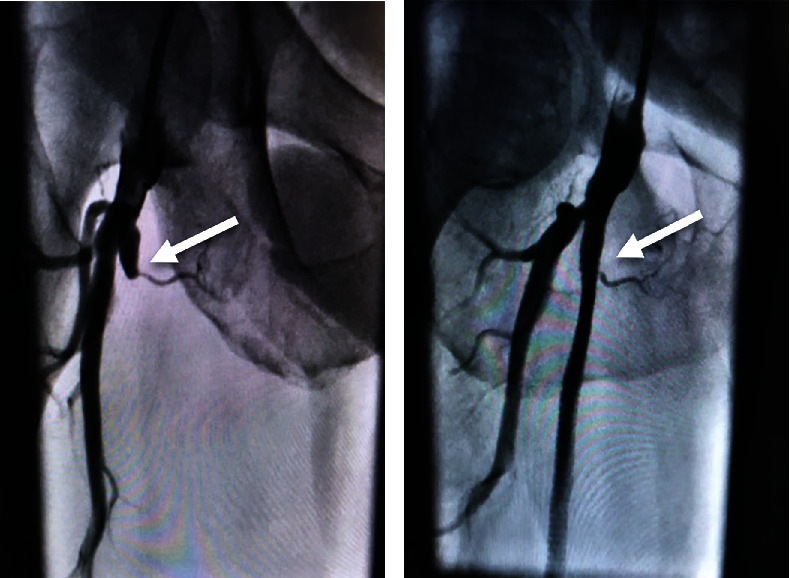

Peripheral arterial disease (PAD) affects more than 230 million adults worldwide. Revascularization via angioplasty is a common method to manage stenosis in the superficial femoral artery (SFA). In-stent restenosis, however, is a common complication in endovascular interventions, especially in the SFA. Here, we present a case that involves recanalization of the SFA in a patient with a previously occluded stent and failed surgical revascularization. This patient initially presented with an occluded SFA which was stented. Four years later, the stent was reoccluded and surgical endarterectomy of the artery was performed with partial removal of the stent. Ten years later, the SFA is again occluded. Recanalization of the SFA using laser atherectomy and restenting of the occluded stent with GORE VIABAHN endoprosthesis was performed successfully. The combination of such methods is a suitable way to manage chronic lesions and minimize restenosis in patients with PAD.

Abstract Image